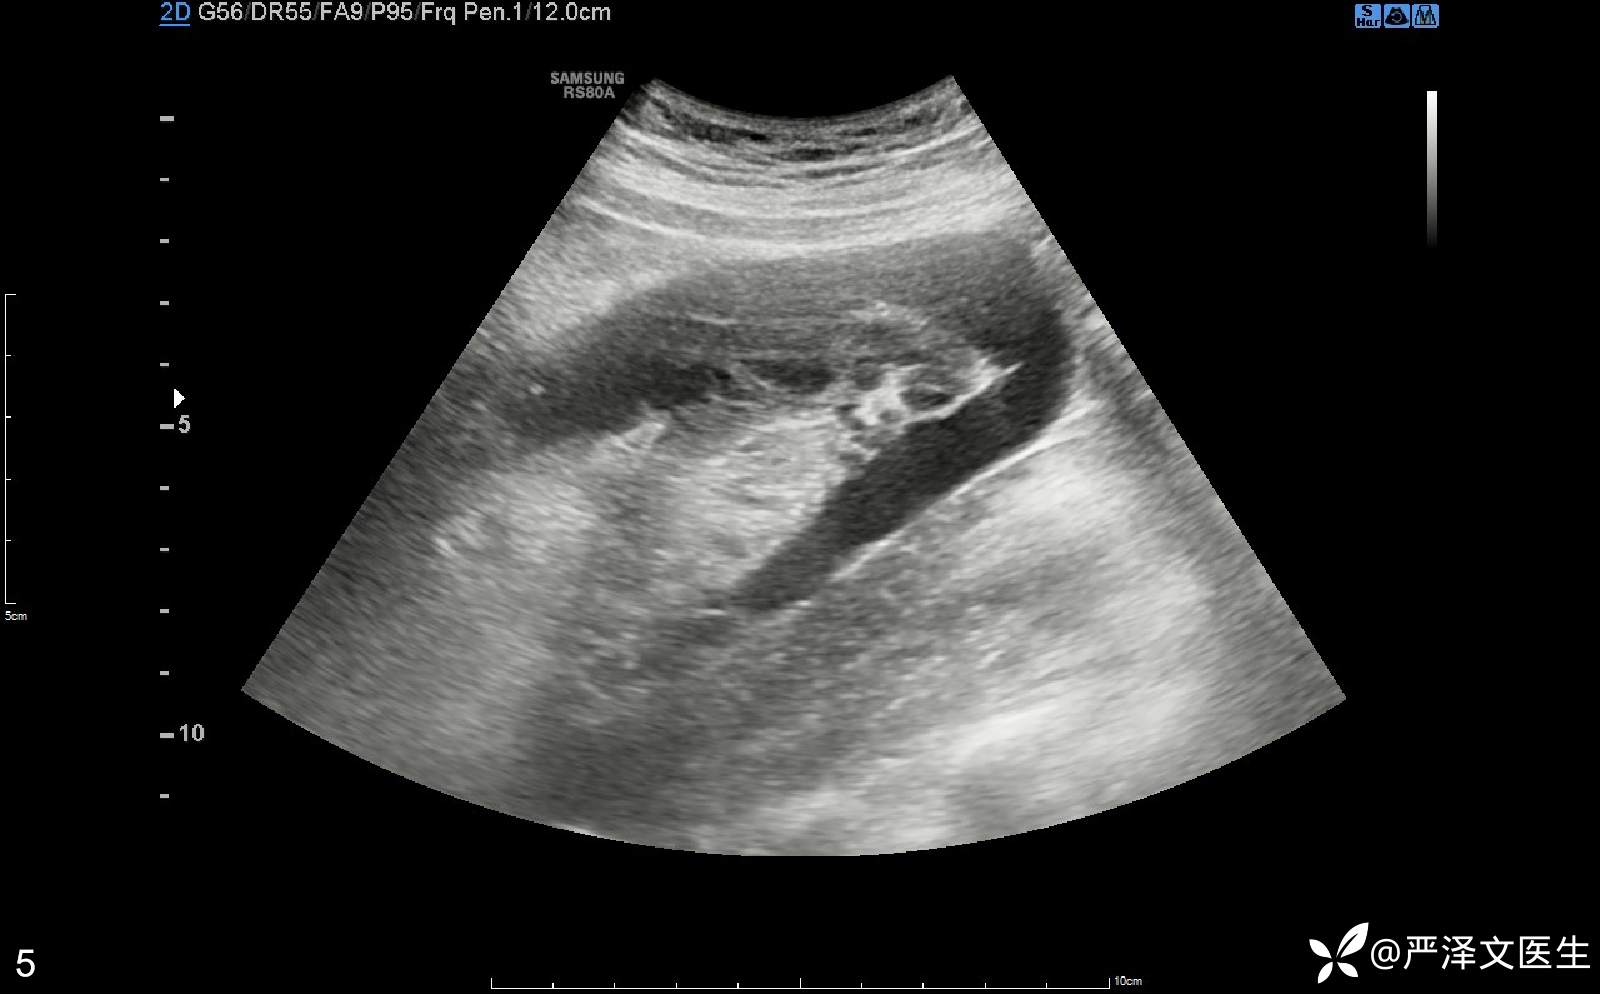

腹部彩超(04-01):(右侧中腹)见混合回声区,大小约69×32mm,边界清,其与血管相连,CDFI:内见血流信号,呈静脉频谱。检查意见:临床所指处(右侧中腹)见一混合回声区,请结合临床。(见图2、3、4、5)

混合回声、增大的阑尾